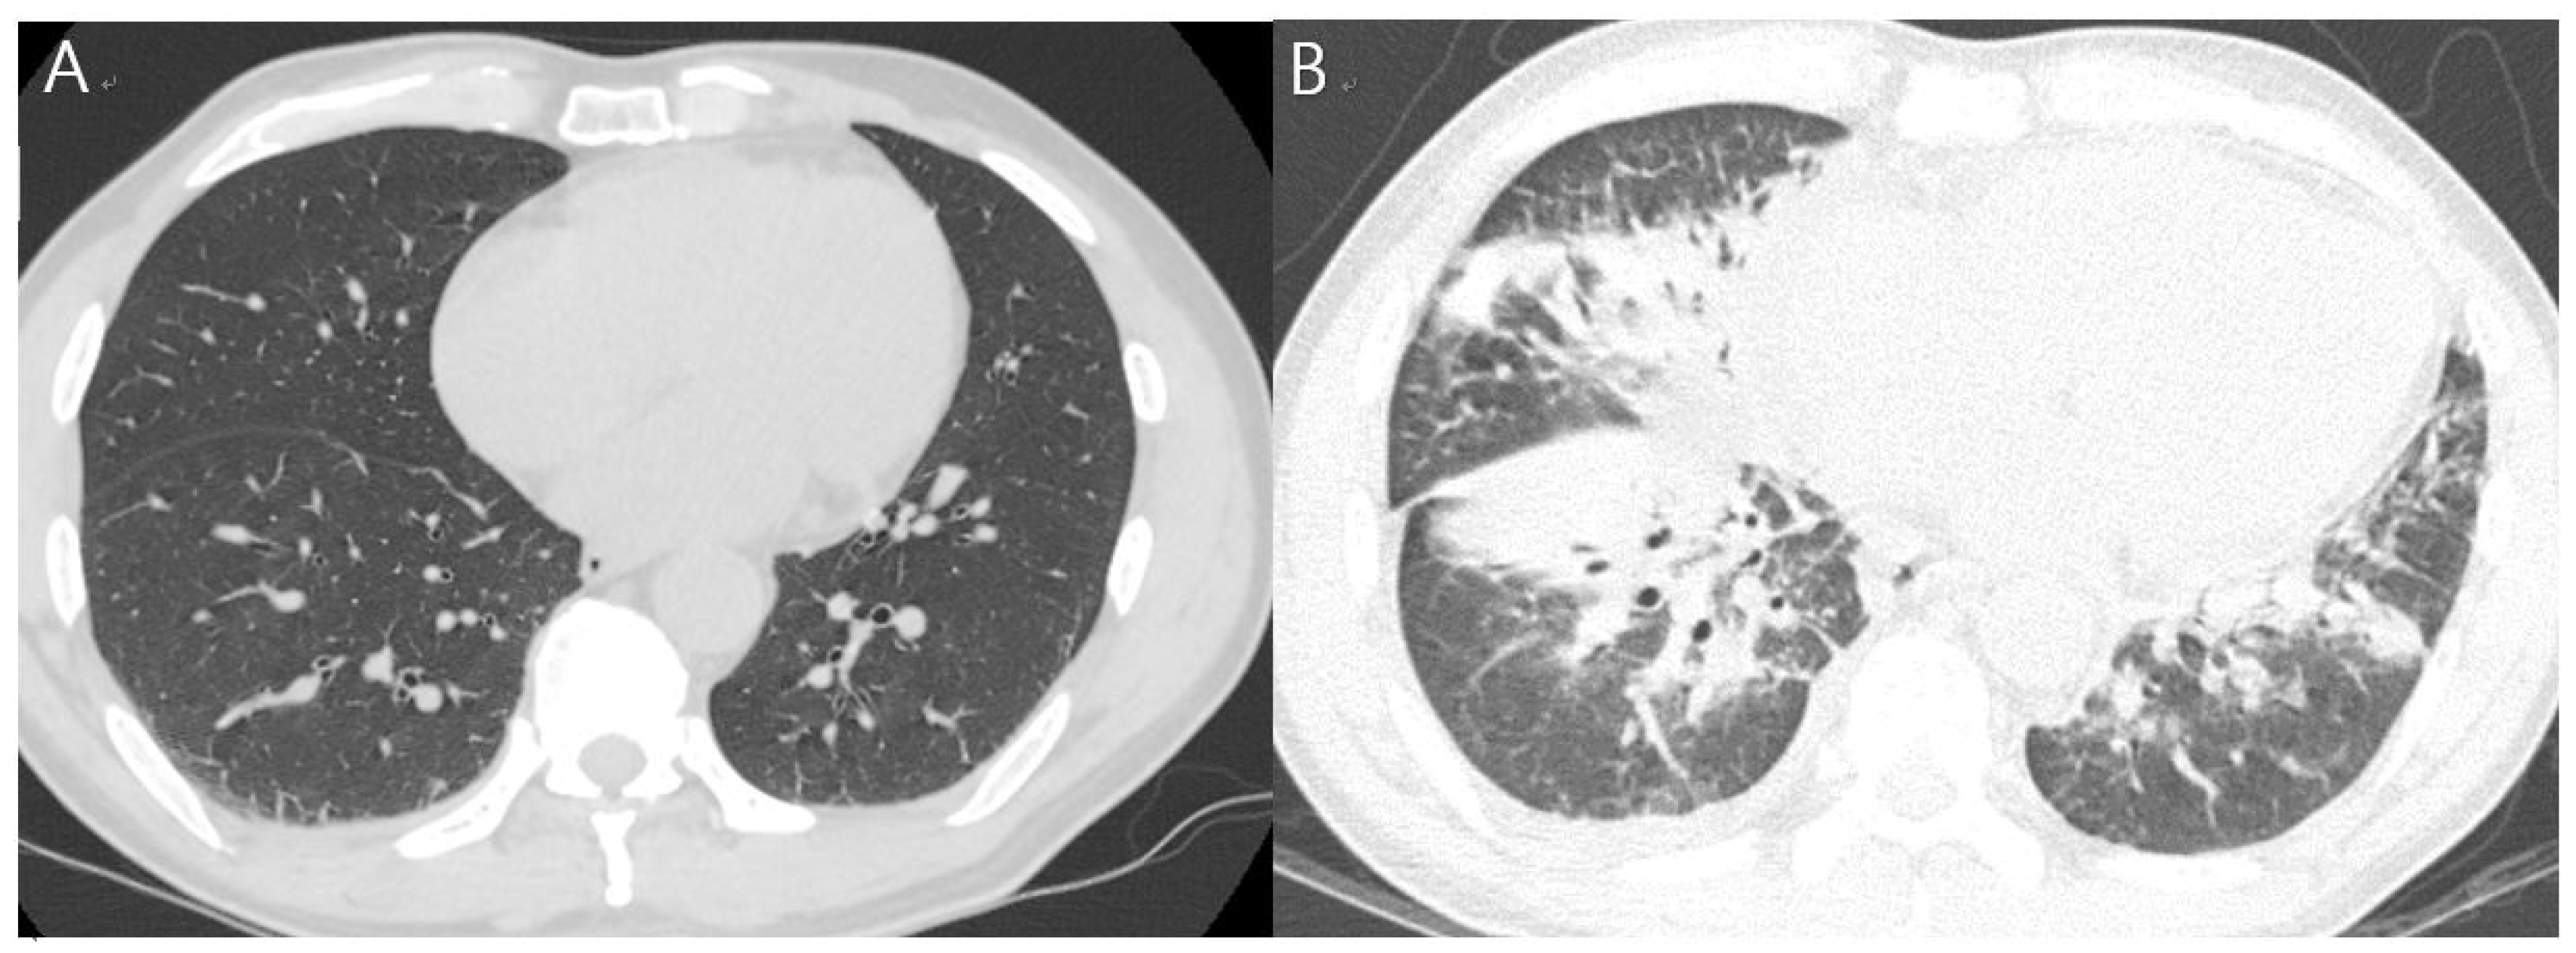

The patient was admitted to the department of respiratory medicine of our hospital and was started on empirical antibiotics (ciprofloxacin and doxycycline). The next day, tests revealed increased levels of WBC (11,540 cells/μL; segmented neutrophils, 88.8%) and hsCRP (24.58 mg/dL). Fever and headache persisted on day 4 of admission, with a further increase in hsCRP levels (34.21 mg/dL). Considering the worsening of the symptoms, the antibiotic therapy was changed to include levofloxacin and piperacillin–tazobactam. A follow-up chest CT on day 6 of admission revealed new findings of extensive lung consolidation and ground-glass opacities in the right lower lobe, with pleural effusion increasing on the right side (Table 1, Figure 1).

Figure 1. Chest computed tomography (CT). (A) Chest CT on admission demonstrating probably dependent atelectasis of the basal aspect of the right lower lobe and (B) on day 6 after admission indicating new-onset extensive consolidation and ground-glass opacity of the right middle lobe, lingular segment, and both lower lobes with increased right pleural effusion.